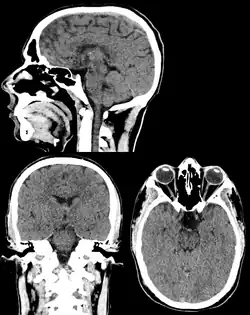

Head & Neck Imaging

CT scan remains the cornerstone imaging modality for the initial evaluation and subsequent management of patients with acute traumatic brain injury due to its rapid acquisition time and high sensitivity for detecting hemorrhagic complications, such as intraparenchymal hematomas and subdural hemorrhages.[56] CT scan of the head is typically used to detect infarction (stroke), tumors, calcifications, haemorrhage.[57] Tumors can be detected by the swelling and anatomical distortion they cause, or by surrounding edema. CT scanning of the head is also used in CT-guided stereotactic surgery and radiosurgery for treatment of intracranial tumors, arteriovenous malformations, and other surgically treatable conditions using a device known as the N-localizer.[58][59][60][61][62][63]